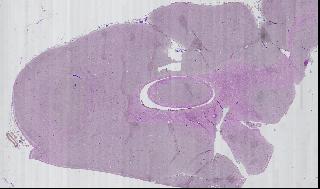

figure

Figure 3. Overview of Slide

Figure 5

Using this tool, we can zoom out to view the entire slide, zoom in on a specific region of a single sample, then view a specific field of vision. Figure 5 is a mosaic of one portion of one slide.